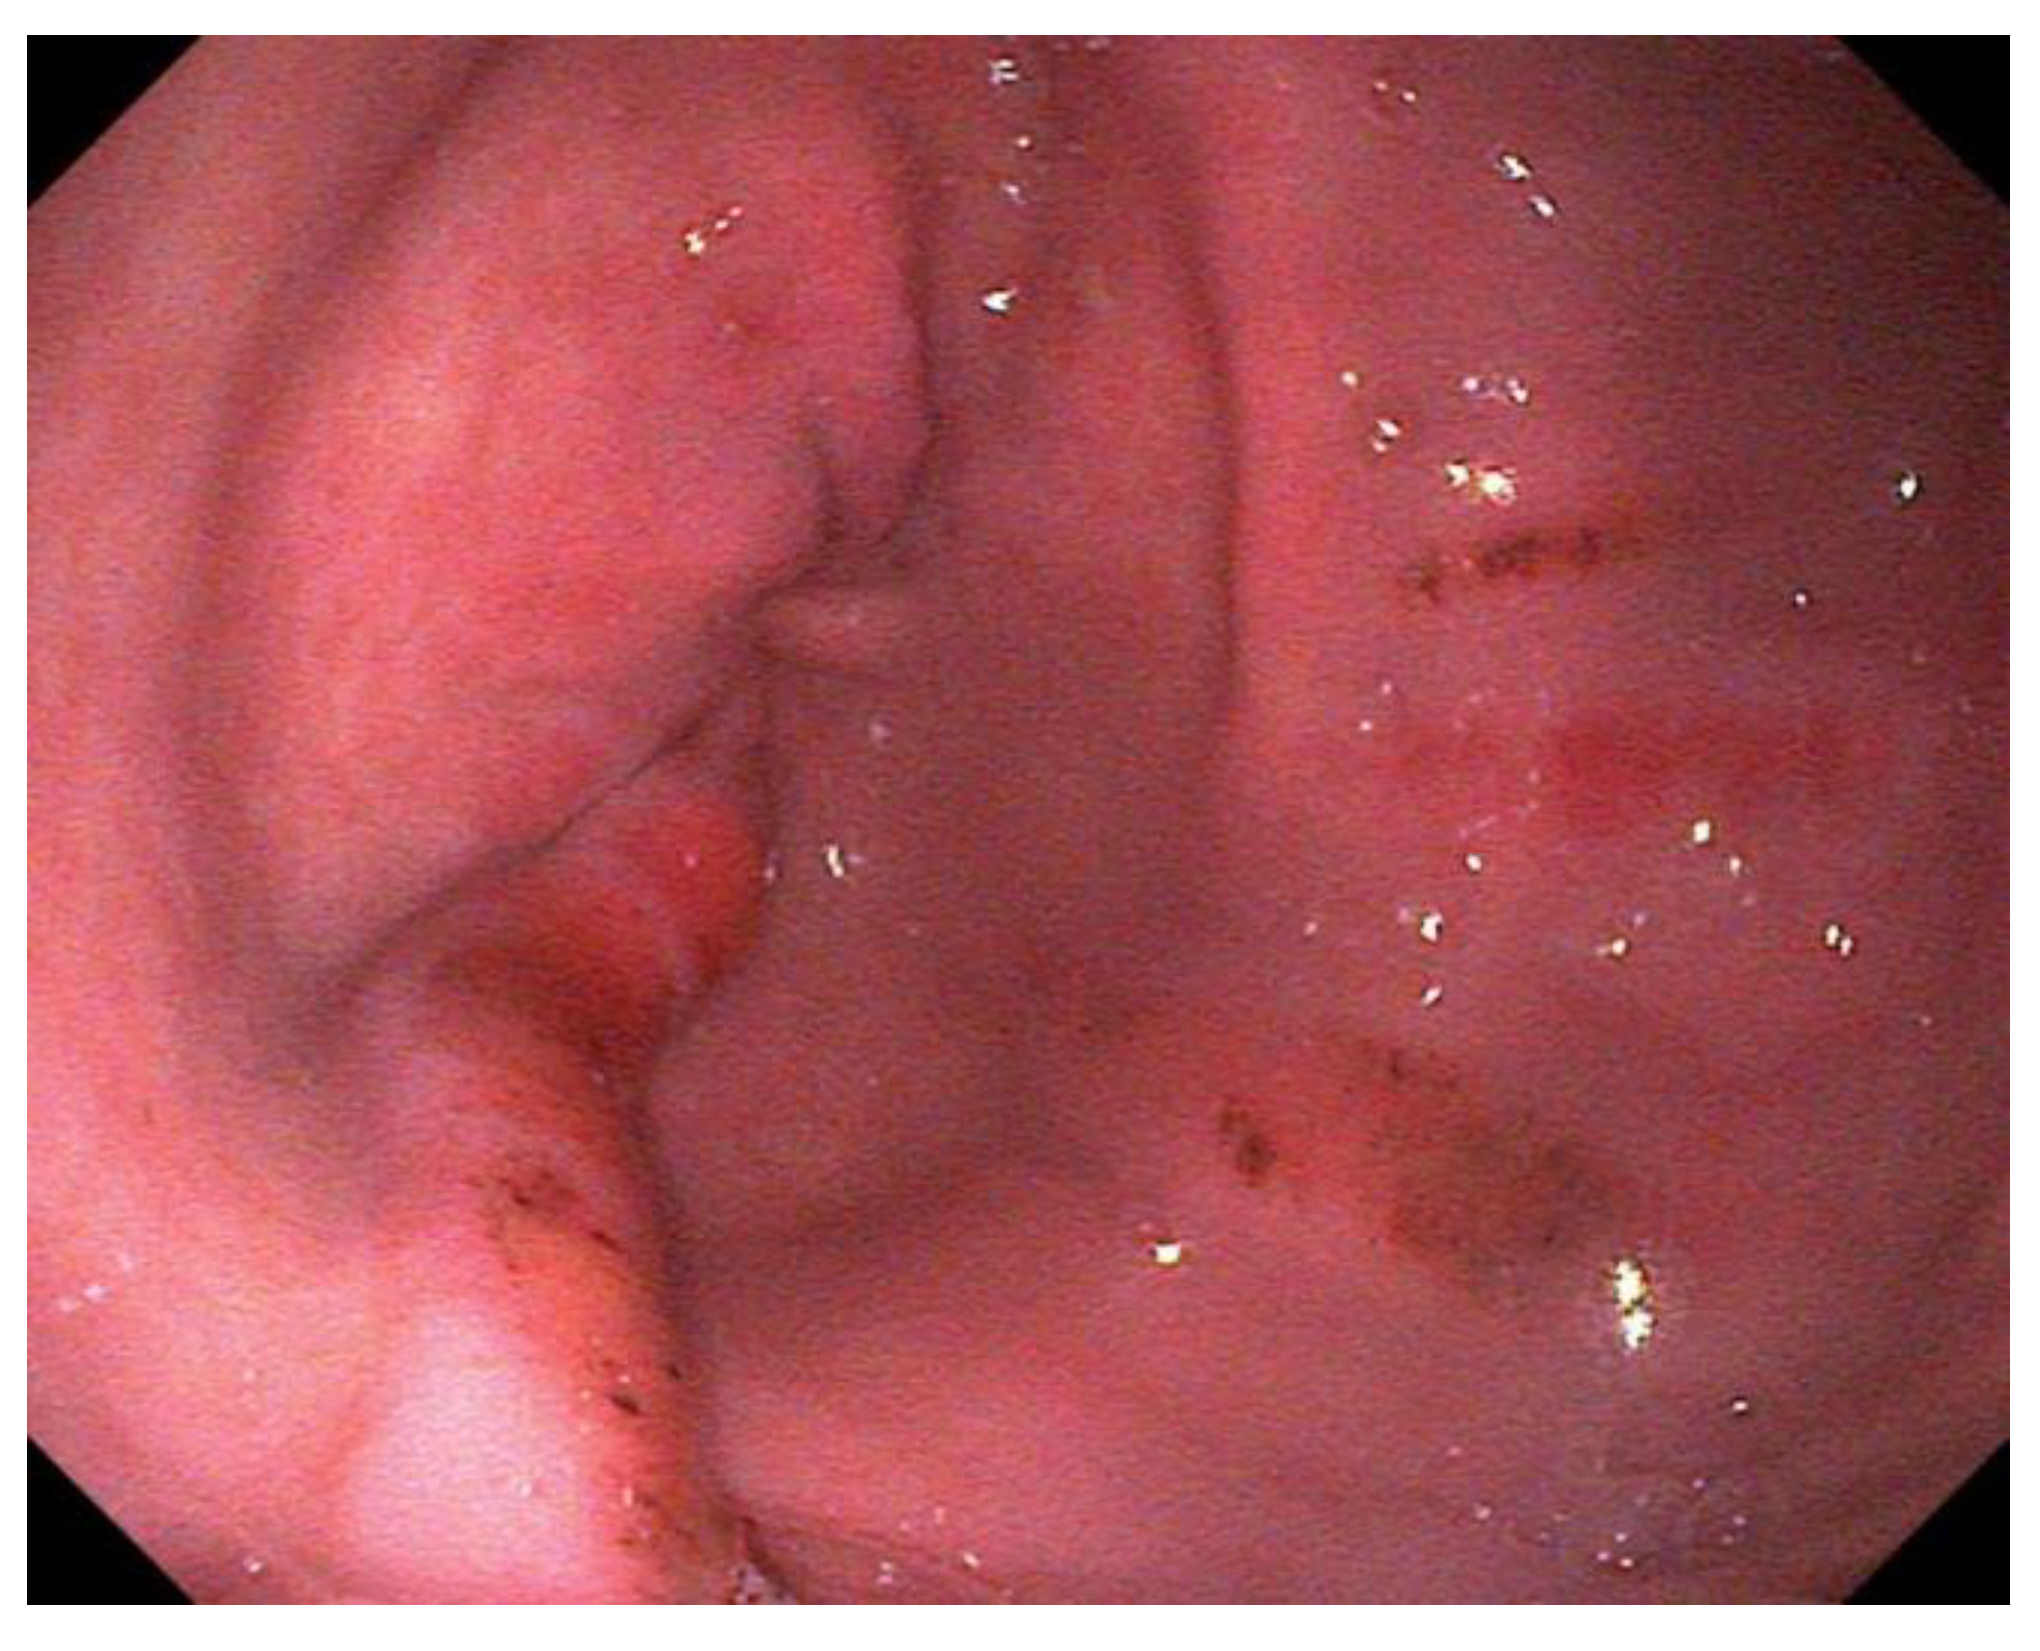

- Grade 2 Small, single or multifocal lesions (Figure 2)